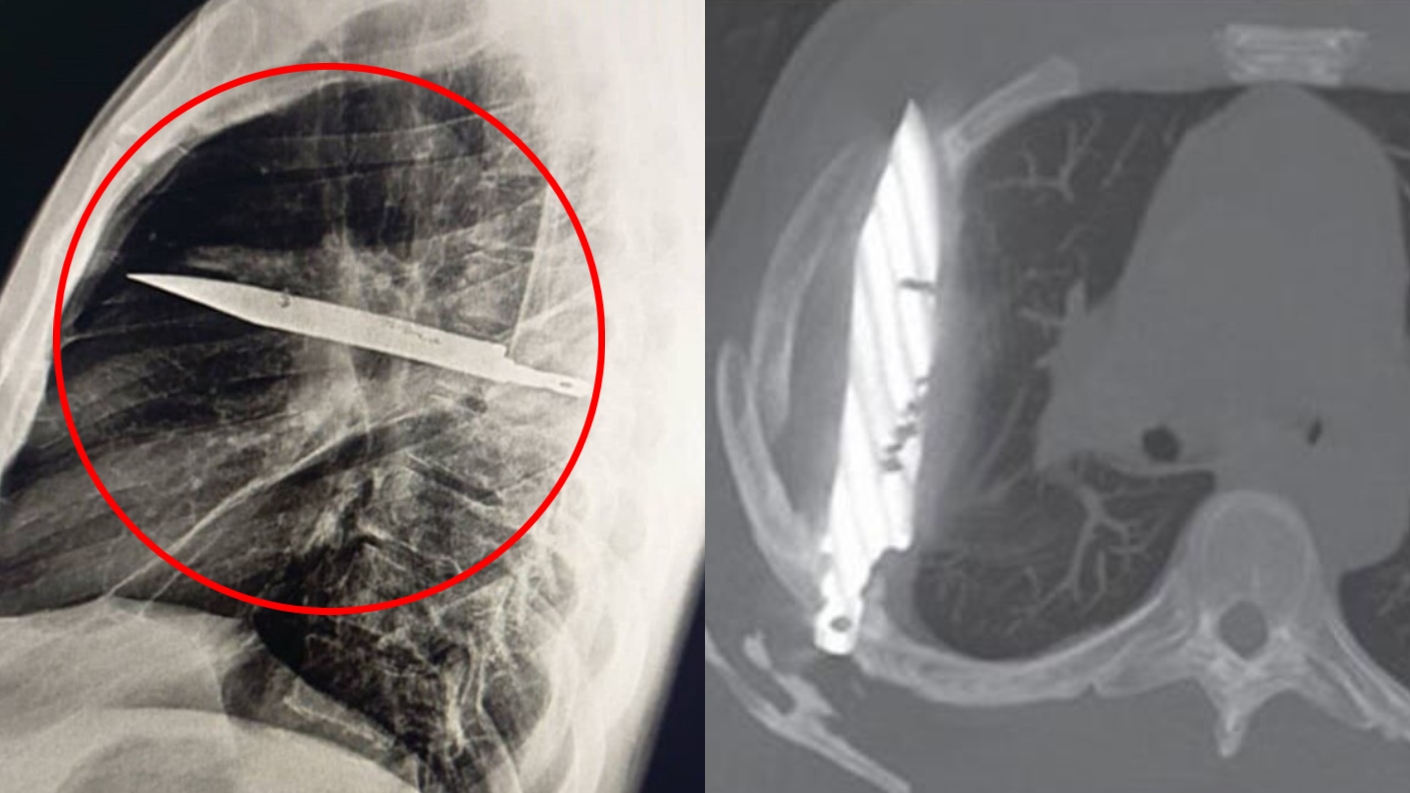

Lo que ni él ni los médicos sabían era que en su pecho tenía una hoja de cuchillo.

El "objeto metálico retenido" era en realidad un cuchillo completo que atravesaba su cavidad torácica: había ingresado por la espalda y deslizado entre la quinta y sexta costilla.